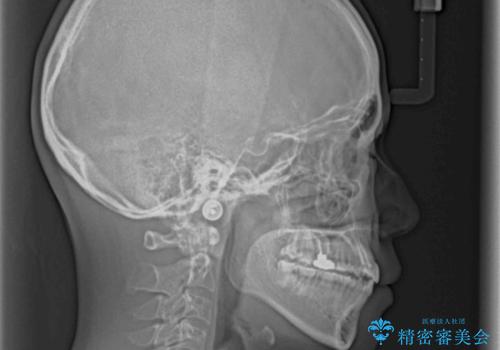

- 上の八重歯を気にして来院された患者様です。

受け口傾向にあるため、上顎前歯の叢生解消とともに下顎前歯を後方へ移動させることを目的とし、上下左右の第一小臼歯4歯を抜歯することとしました。

受け口傾向の方の下顎抜歯矯正では、下顎前歯の歯肉が退縮することがあります。前歯を移動させるときには、歯肉退縮が起こらないように工夫する必要があります。